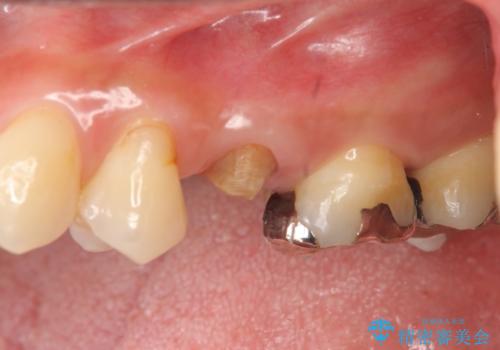

放置し崩壊した歯 セラミック治療による咬合機能回復

- 忙しくて歯科医院に通えず、ついに歯が折れてしまい治療を希望され来院されました。

虫歯を丁寧に除去したのち、なんとか歯を残せる見通しがたったので根管治療を行いセラミック補綴を行いました。